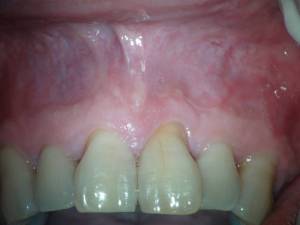

Después de realizarle un tratamiento de conductos  a la pieza 2.1 que presentaba una periodontitis apical crónica que fístulizaba, el paciente nos llegó los 4 meses con una nueva presencia de la fístula.

Con un aparente, buen tratamiento de conductos, estaría indicado una cirugía endodontica frente a este fracaso endodóntico por vía ortógrada, ya que necesitaríamos la ayuda de una obturación retrógrada.